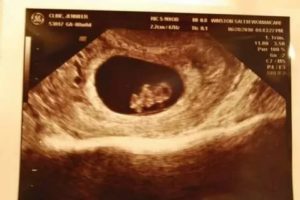

УЗИ: 10 недель беременности

Как правило, 10 неделя беременности не является сроком для проведения планового УЗИ. Но если по какой-либо причине (к примеру: уточнение срока или контроль беременности) УЗИ проводится на десятой неделе, то вас ожидает встреча с необыкновенным чудом!

Попросите врача сделать фото УЗИ 10 недель беременности, где хорошо заметно, что размеры будущего малыша на этом сроке можно сравнить с размером средней сливы. И хотя плоду еще так мало времени, но он уже напоминает настоящего крохотного человечка.

Что происходит на 10 неделе беременности?

С помощью УЗИ вы увидите четко проступающее очертание тельца своего малютки, хорошо различимы его миниатюрные ручки и ножки, заметны даже локотки и лодыжки крохи!

Этот маленький обитатель вашего живота может самостоятельно втягивать губки, выплевывая и заглатывая околоплодную жидкость, закрывает и открывает свой ротик. Малыш уже может махать согнутыми в локотках ручками, разгибать маленькие кулачки, передвигать и подгибать под себя ножки.

Представьте, сколько всего интересного и удивительного сможет узнать и увидеть при ультразвуковом исследовании мамочка на 10 неделе беременности!